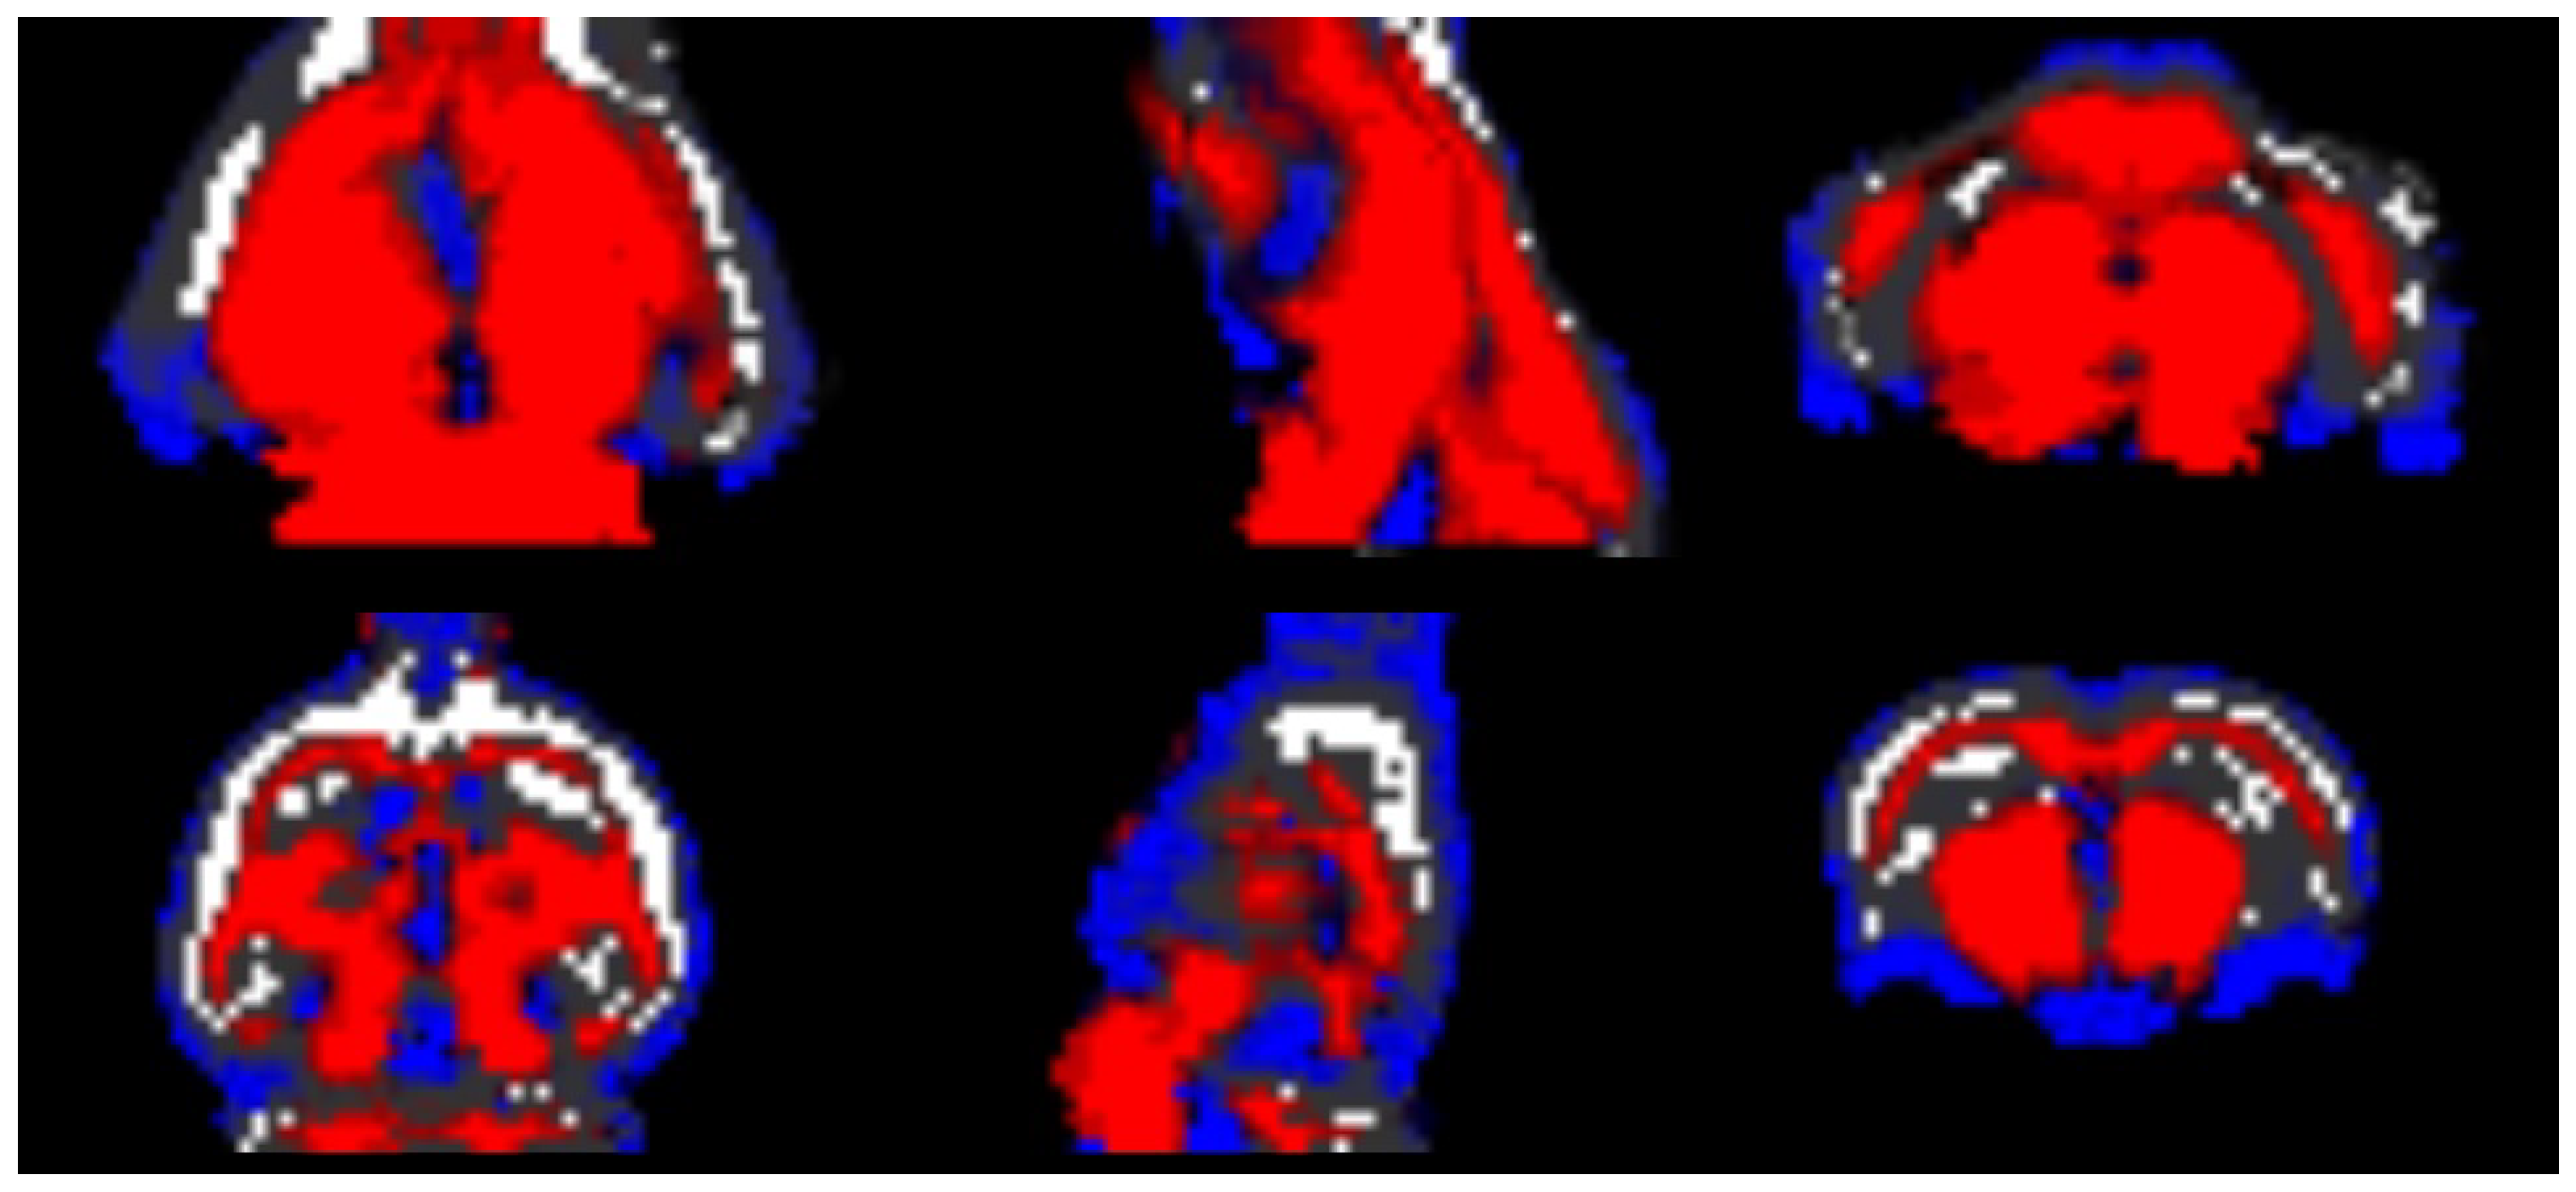

After generating the scans for the final test, a selection was made to ensure that all scans had correct anatomy, i.e., whether the SPM12 software could—or could not—generate the GM, WM, and CSF labels. About half of the randomly generated scans had structural defects, and the SPM software was not able to create the GM, WM and CSF labels correctly. This is the main weakness of this work and should be improved in a future work; however, it can easily be overcome by a quick visual inspection to discard the imperfect scans. It was also tested whether SPM could create the labels of the synthetic data generated by the remaining models. It was found that almost all the scans generated by -WGAN_ADNI had problems in creating the labels, so the proposed methods, i.e., the new loss functions and the normalisation layer were able to improve the quality of the generated scans, as can be seen in Figure 10.

Figure 10.

Semantic masks built with the SPM12 software. The semantic mask in the first row was built using a scan generated by the -WGAN_ADNI model, and the semantic mask in the second row was built using a scan generated by the -WGANSigmaRat2 model. The blue colour is the CSF, the red colour is the WM, and the grey scale is the GM.